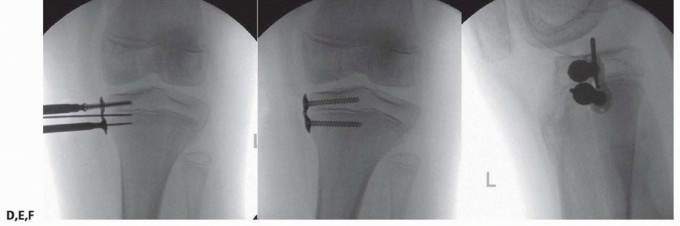

- ###

- FIG 8 • A,B. A 12-year-old boy with spastic diplegia who ambulates with a crouch gait, hamstring contracture, and knee flexion contracture. C,D. Intraoperative fluoroscopy demonstrating preoperative PDFA. The child underwent hamstring transfer and distal femoral guided growth with placement of 6.5-mm cannulated screw positioned anterior in the center of the distal femur. E,F. Postoperative lateral radiographs show improved PDFA and full extension on clinical examination. (Courtesy of UW Pediatric Orthopaedics.)

- ### Screw choice ▪ In obese patients, it may be desired to use stainless steel or solid screws to avoid fracture of the screw. This tends to happen at the metaphyseal location (FIG 9)

- FIG 9 • A 9-year-old boy with juvenile Blount disease and distal femoral and proximal tibia deformity was indicated for guided growth. In this method, lateral epiphysiodesis was performed by placing guide pins for cannulated screws into the epiphysis and solid screws were placed in the metaphysis. The metaphyseal screws are prone to failure, which is why solid screws were chosen. (Courtesy of UW Pediatric Orthopaedics.)